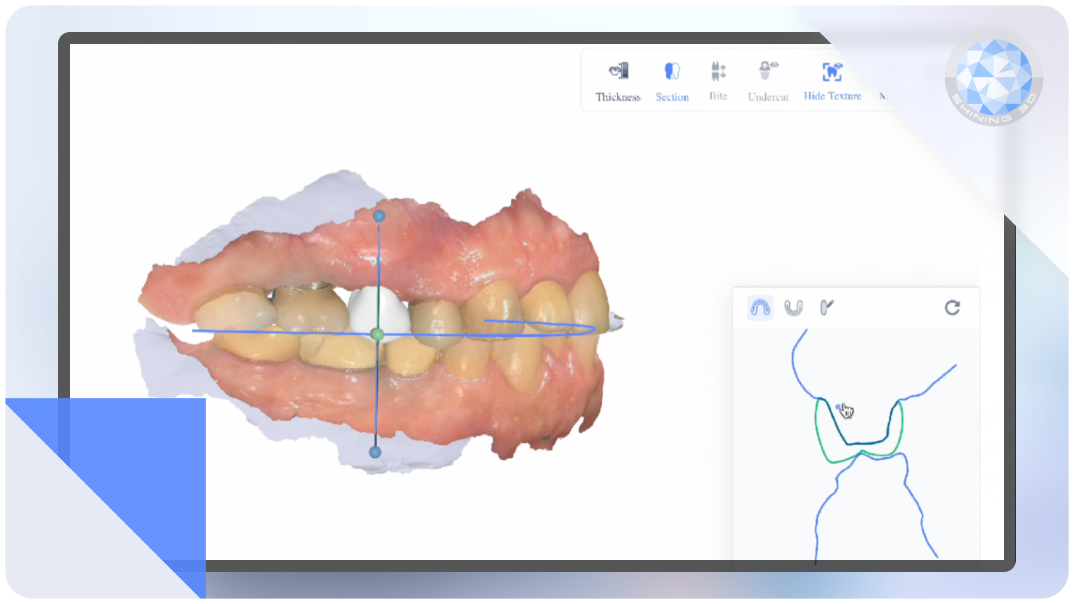

AI 3D Model

Covers partial arch, full arches, ABO basic models, and quadrant arch models—versatile and impeccably accurate.